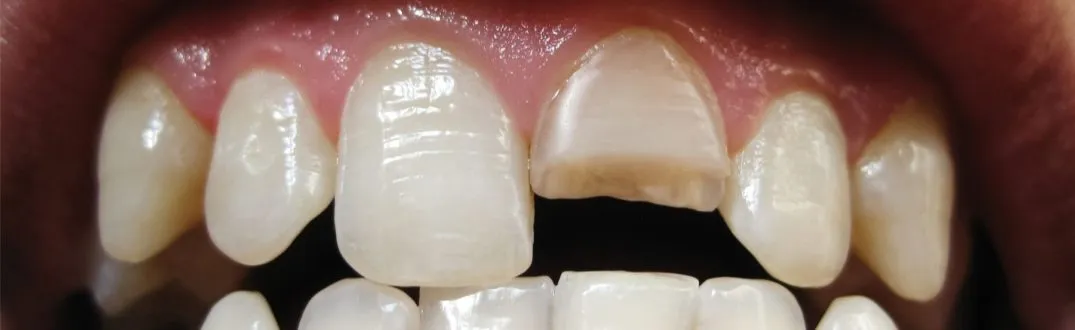

Pęknięcie korony a pęknięcie korzenia poznaj fundamentalną różnicę

Zanim zagłębimy się w szczegóły dotyczące pękniętego korzenia, warto zrozumieć kluczową różnicę między tym uszkodzeniem a pęknięciem korony zęba. Pęknięcie korony, choć może być bolesne i wpływać na estetykę uśmiechu, zazwyczaj dotyczy widocznej części zęba. Często można je naprawić za pomocą wypełnienia, licówki lub korony protetycznej. Pęknięcie korzenia jest jednak znacznie poważniejszym problemem. Dotyczy ono ukrytej części zęba, która znajduje się w kości szczęki. Takie uszkodzenie jest trudniejsze do zdiagnozowania i znacznie trudniejsze do wyleczenia. Rokowania w przypadku pęknięcia korzenia są zazwyczaj gorsze, a szanse na uratowanie zęba zależą od wielu specyficznych czynników.